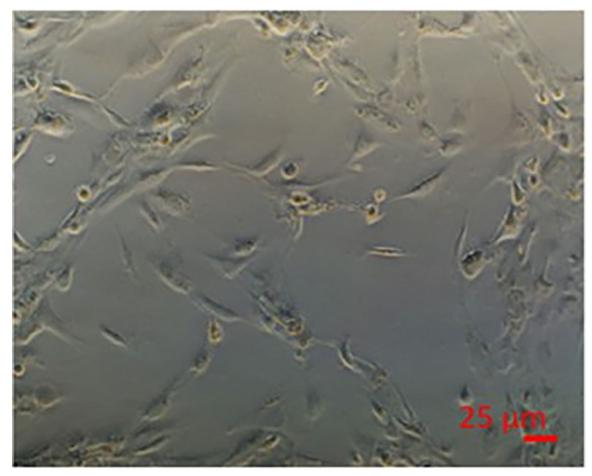

图 2:NPCs 在 Hep 培养基中形成小叶样结构

该图显示 NPCs 的培养特征:NPCs 在 Hep 培养基中培养 7 天后,可自发形成类似体内肝脏的小叶样结构(lobule-like structures),倒置显微镜下可见细胞有序排列,无明显团聚或凋亡。这一结构是肝脏微环境的关键特征,为后续与肝细胞共培养奠定了 “结构基础”,且无需额外添加细胞外基质(ECM)—— 研究证实肝星状细胞可自主合成足量 ECM,外源性 ECM 反而可能干扰细胞天然生化过程。